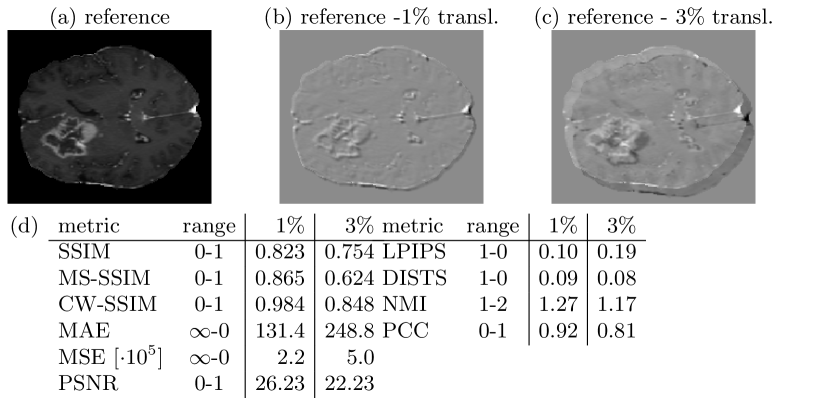

3.2 Pitfall 2: Similarity of Misaligned Images

In image-to-image translation, the source domain input image and the target domain image are often misaligned, because both images were acquired at different timepoints or even with different devices. Therefore, an image synthesized from a misaligned input image is also often misaligned. However, in most cases, medical images are perceived as similar and interpreted in the same way, regardless of small spatial misalignments. Fig. 2 shows that small translations, that are hardly visible, significantly affect most metric scores. Only CW-SSIM and DISTS do not show large changes as they were designed and reported to be less sensitive to misaligments.

Refer to caption

Figure 2: Small misalignments have strong influence to all reference metrics. Only DISTS and CW-SSIM are less sensitive to small geometric transformations.